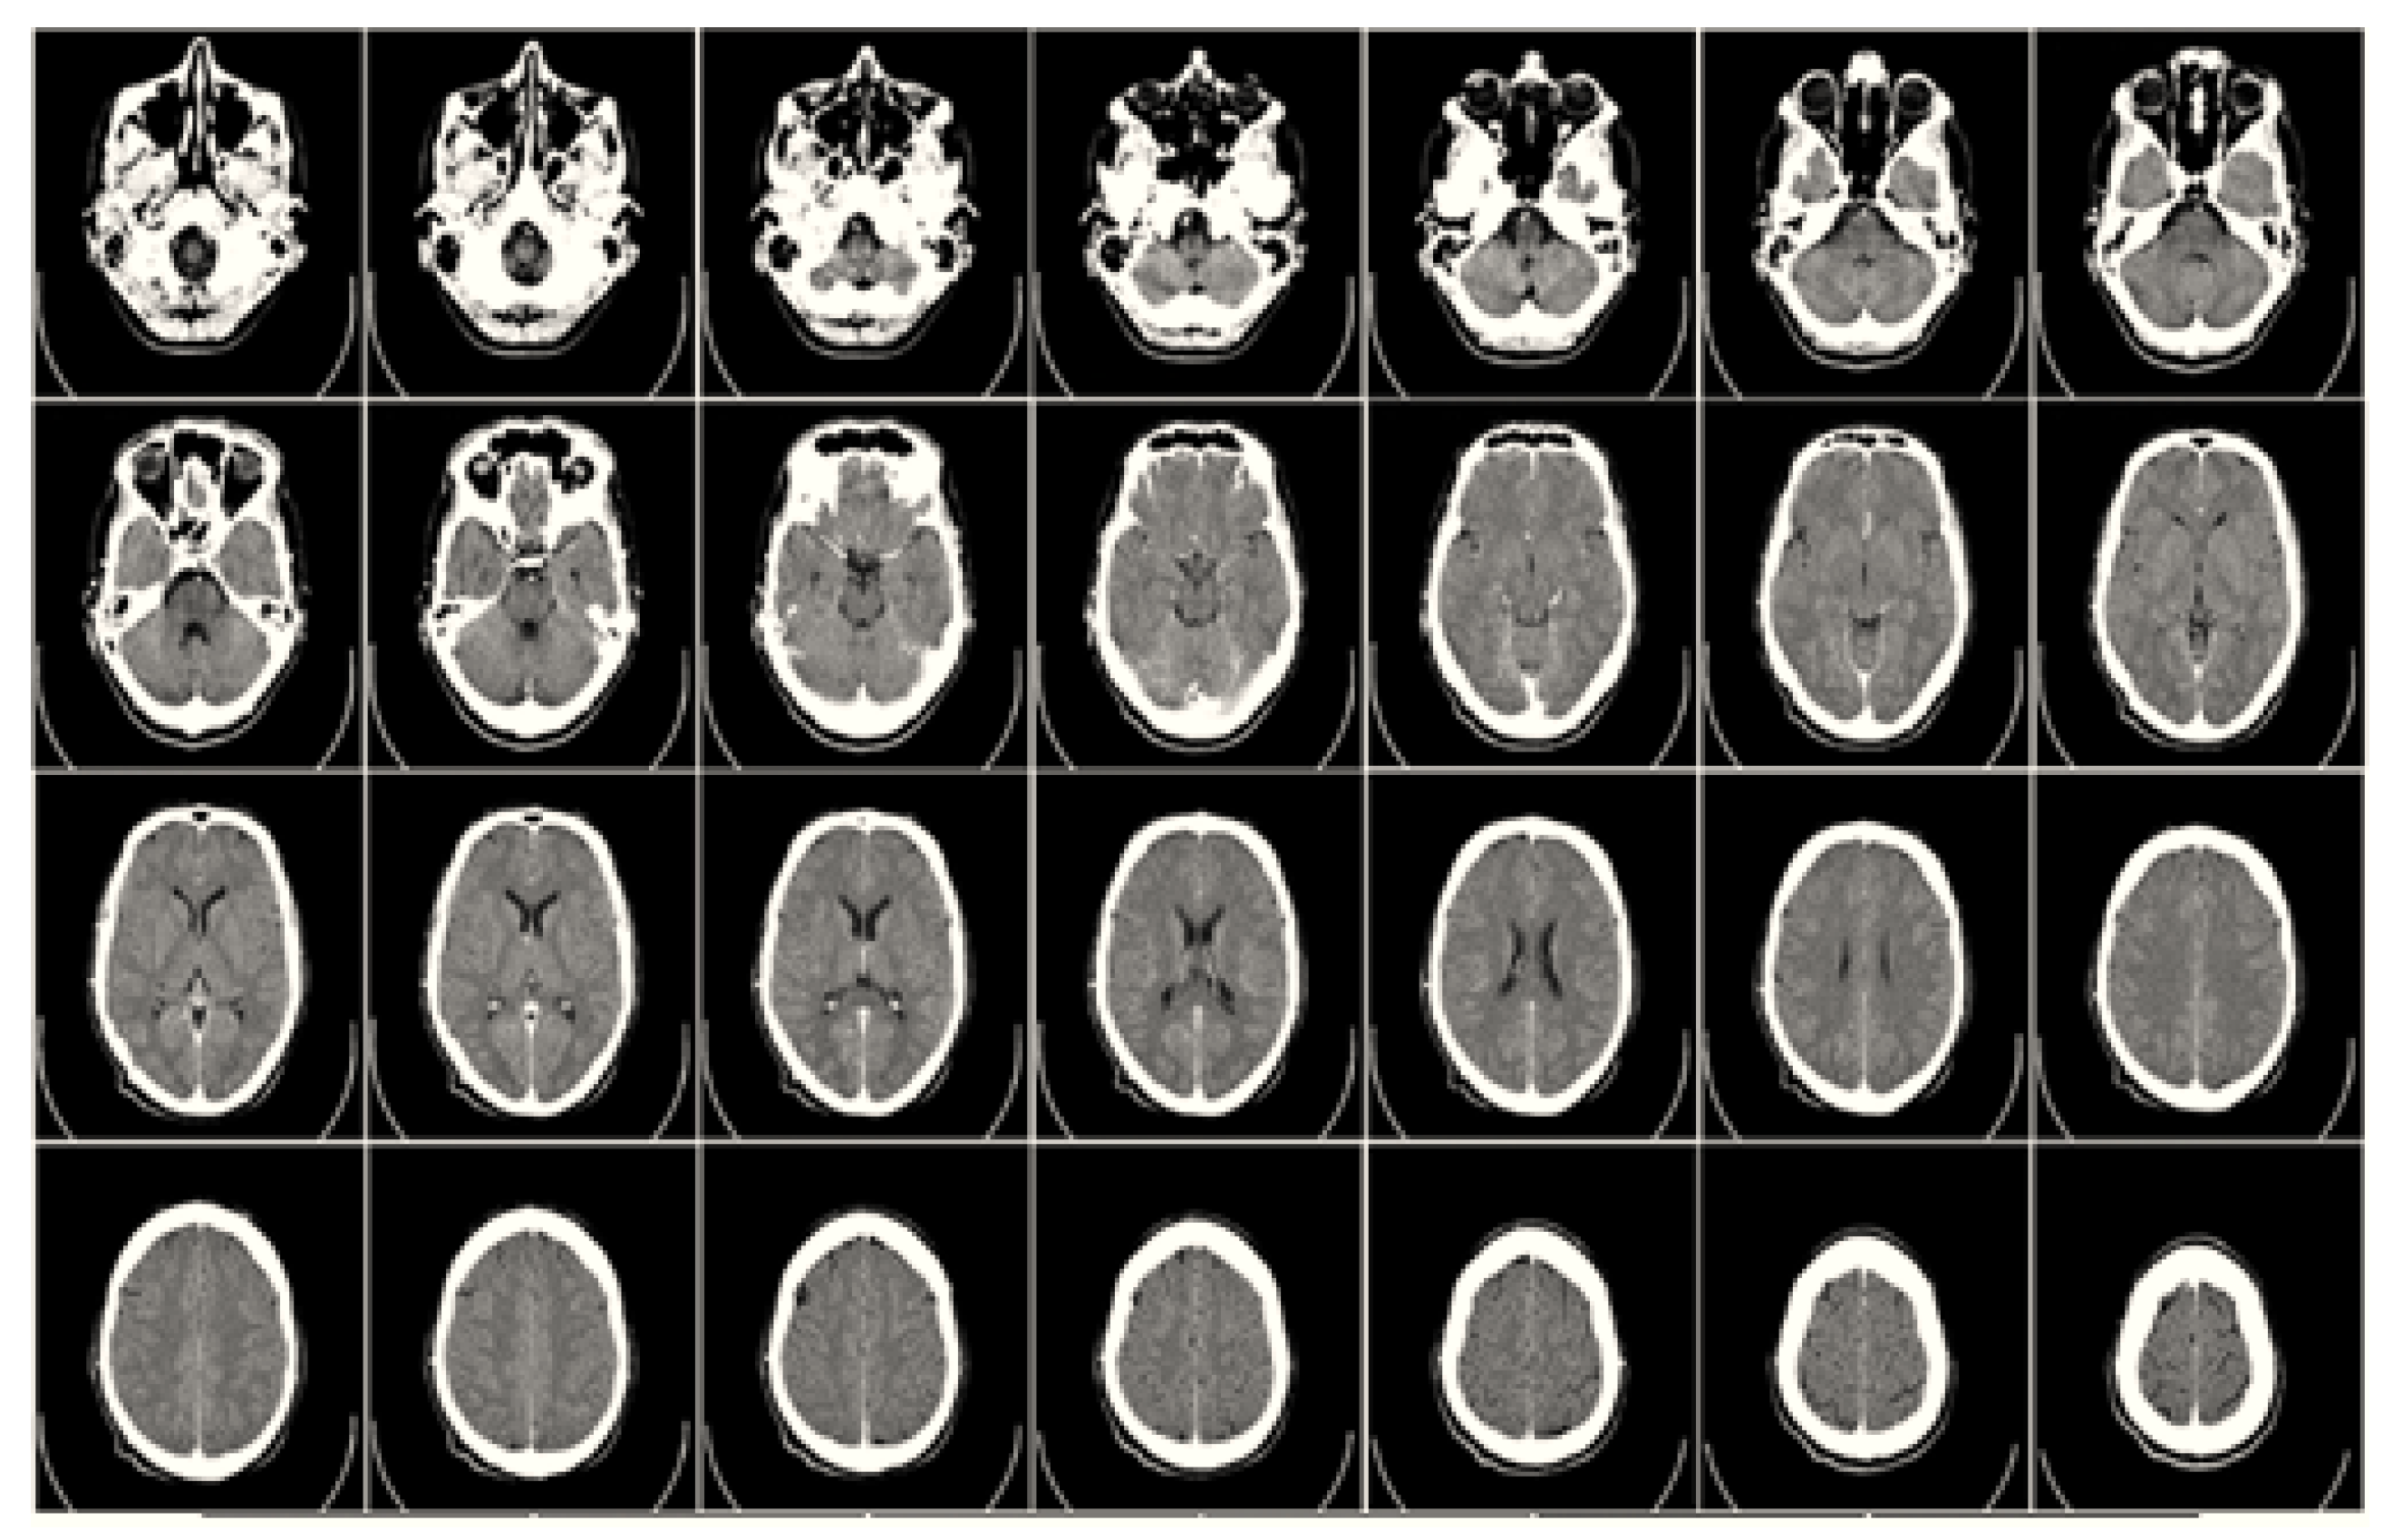

2.1. Computed Tomography (CT)